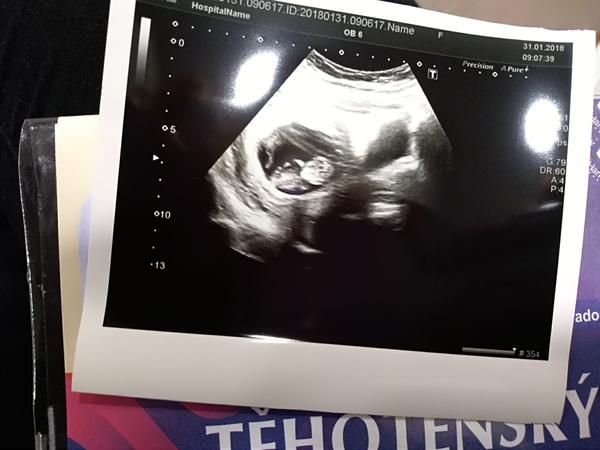

Tak já jsem konečně po kontrole 🙂 Nakonec je miminko starší,než jsem myslela (10+6tt) a má skoro 4cm 🙂 Příští týden nás čeká 1.screening a 9.2. 5D UTZ kvůli genetice.